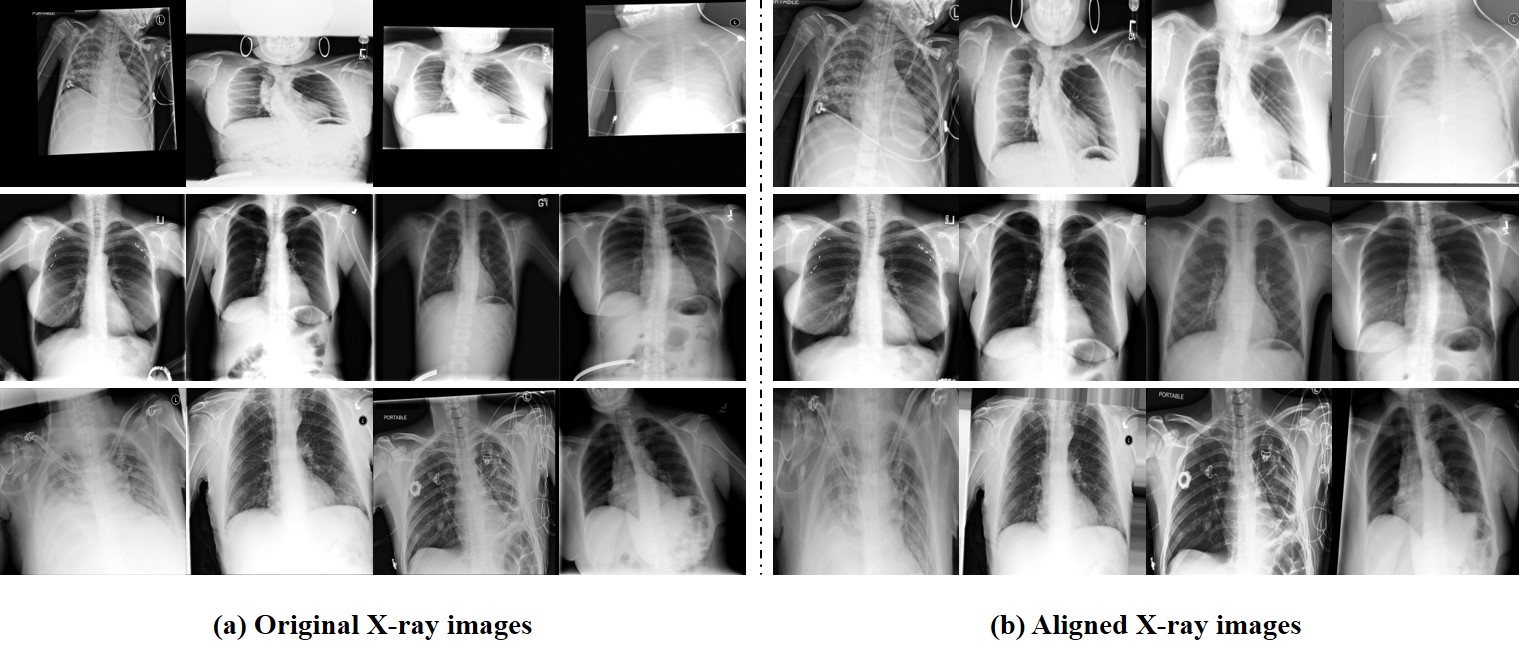

Figure 4: Examples of original X-ray images and aligned X-ray images. (a) The incorrectly aligned original X-ray images. (b) The improved X-ray images from the alignment module.

The original X-ray image generally contains diverse types of variations such as rotations, shifts, and different scales. These misaligned X-ray images are commonly found in various chest X-ray datasets [18, 33, 34] and make it hard to find the disease occurrence areas for generating the disease masks. Moreover, these variations function as noise in the deep network, making it challenging to identify disease and causing the proposed disease masks to guide the network to the wrong area.

To solve this problem, we use an alignment module [21] that reduces the variations in the original X-ray images. The alignment module applies an affine transformation to the original X-ray images to generate aligned X-ray images. Fig. 4 shows some examples of original and aligned X-ray images. In Fig. 4(a), the original X-ray images contain diverse variations, but Fig. 4(b) shows higher-quality X-ray images obtained from the alignment module with effectively reduced variations.